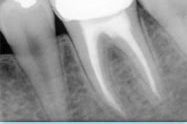

Las coronas dentales

Las coronas dentales son las más populares para reemplazar los dientes rotos, en el caso cuando la raíz es bastante saludable para ser utilizado como apoyo.

Las coronas dentales ayudan a restaurar el diente dañado, protegen los dientes sensibles, evitan el agravamiento de la situación cuando no se puede hacer nada con la ayuda de los empastes dentales y cuando no se puede corregir la forma del diente o su color.